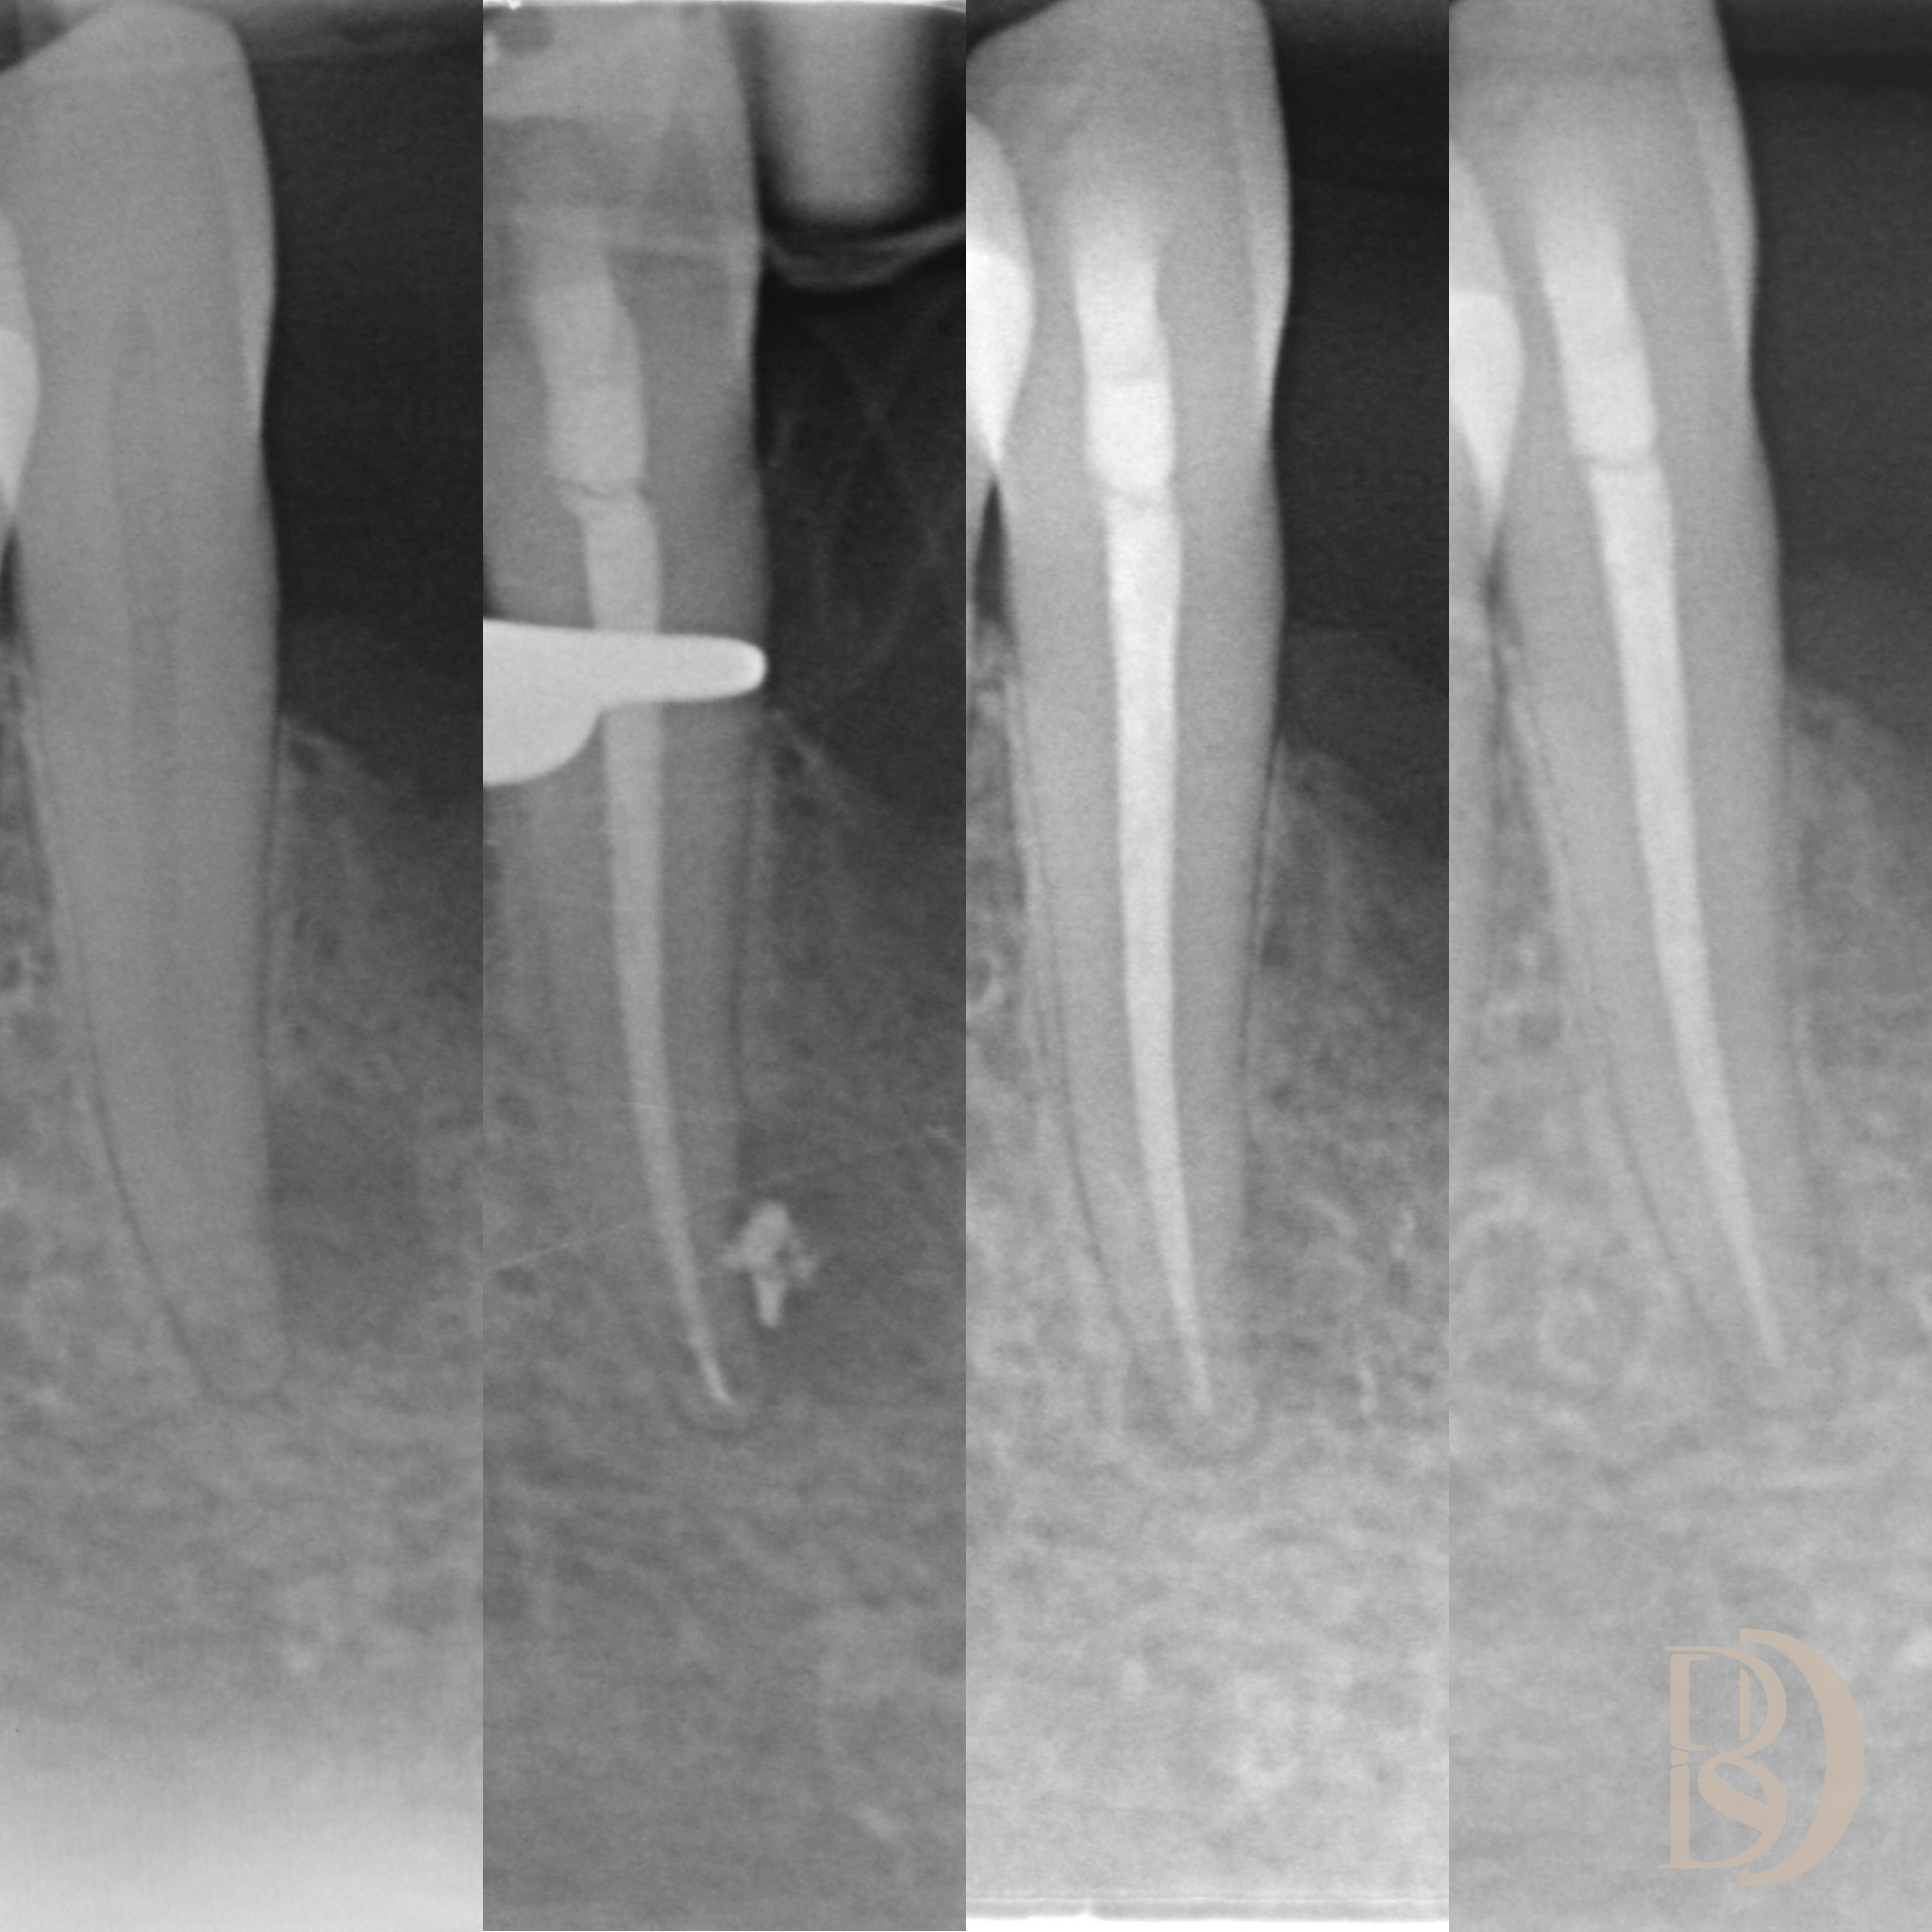

Some examples of Dr Fred’s Endodontic cases:

X-ray dental images showing four views of a tooth with a root canal treatment.

Dental X-rays showing tooth root structures and dental instruments in place.